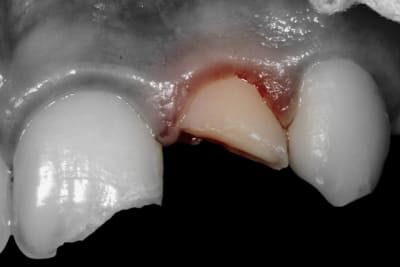

Enfant de 12 ans adressé par son dentiste le lendemain d'un trauma avec fracture de 21 et 22.

- 21 est une incisive mature mais jeune. Les cornes pulpaires sont très proéminentes et une fracture même d'apparence minime a donc une implication pulpaire directe. Il faut recouvrir en urgence le trait de fracture : ici par un CVIMAR (Fuji II LC). Une restauration par résine composite sera réalisée.

- 22 présente une exposition pulpaire ancienne de 20 heures. 20 heures donc que les germes buccaux contaminent directement la pulpe, heureusement jeune et donc avec un fort potentiel de défense.

Le fragment fracturé, récupéré par la maman, est collé.